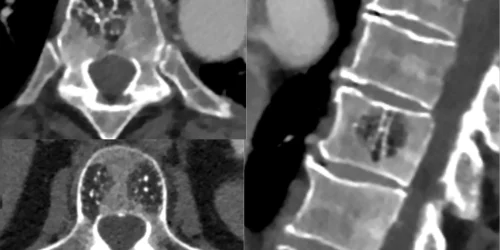

MRI is the most helpful diagnostic test for evaluating neck pain after car accidents because it shows:

- Annular Tears: Tears in the disc’s outer layer that may not be visible on X-rays

- Disc Herniations: Nucleus pulposus material that has herniated through tears

- Facet Joint Damage: Injury to the small joints behind the discs

- Ligament Injuries: Damage to stabilizing ligaments

- Nerve Compression: Herniated material or bone spurs contacting nerve roots

- Spinal Cord Status: Any compression or injury to the spinal cord itself

This is a critical point that many patients and even some physicians misunderstand. MRI alone cannot provide a diagnosis because:

- Asymptomatic Abnormalities:Over 90% of asymptomatic people show disc abnormalities on MRI imaging. Your MRI may reveal findings that are completely unrelated to your pain.

- Multiple Findings: Your MRI may show herniations at several levels, but only one or two might be causing your symptoms

- Severity Mismatch: Small herniations can cause severe pain if they’re actively inflamed, while large herniations with stable tears may cause no symptoms

- Imaging Limitations: MRI shows structure, not function or pain generation